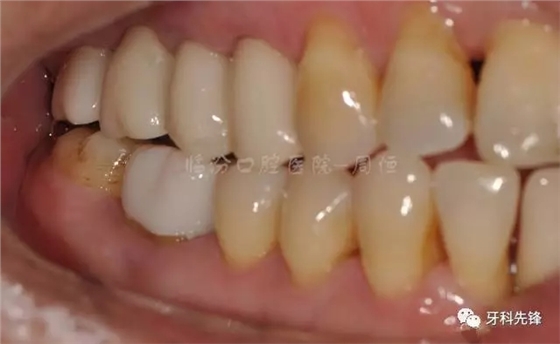

圖2 術(shù)前側(cè)位咬頜照

640.webp (3).jpg